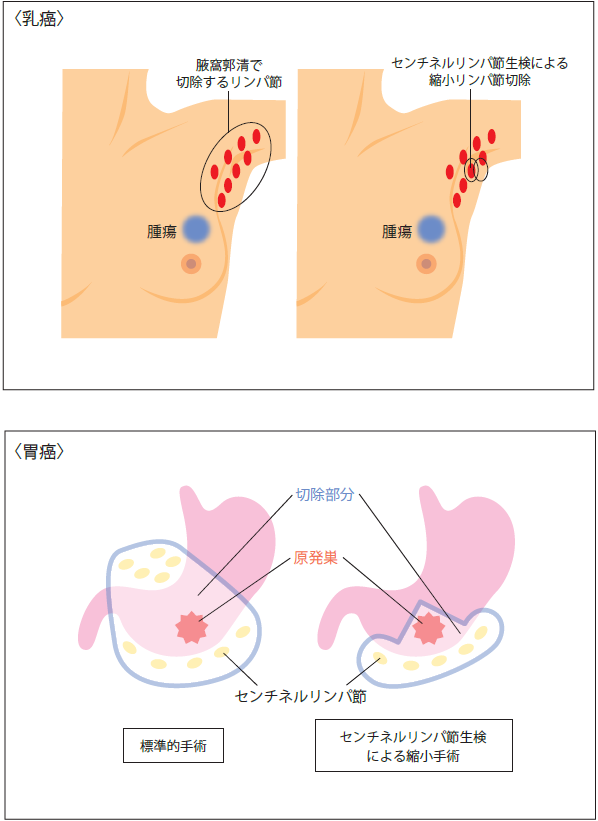

「がんの診断方法」には、画像検査や腫瘍マーカーなどがあるが、最終の確定診断は、腫瘍の一部を切り取って、がんかどうかを判定する病理診断である。多くのがんはリンパ節を介して転移していく。このリンパ節の中でも、原発巣から一番近い位置にあるリンパ節を「センチネルリンパ節」と言う。「センチネル」とは「見張り番」を意味する言葉で、このセンチネルリンパ節に転移が見られない場合、切除する範囲が小さくてよい。そのため患者の負担が少なく、回復も早くなる。

▲センチネルリンパ節による縮小手術